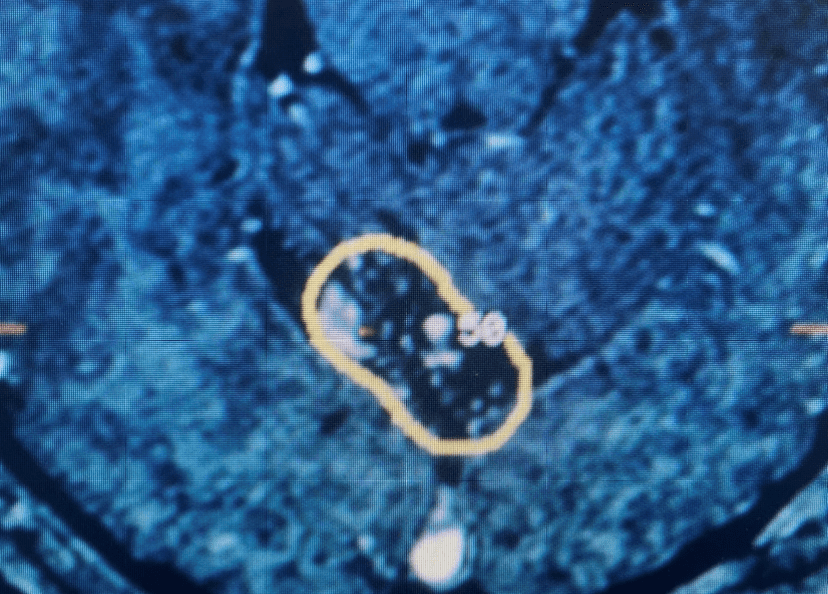

Figures 1a and 1b. Sagittal T2 MRIs of the lumbar spine demonstrating L2-3 stenosis after L3-4 instrumented fusion.

This 62-year-old female presents with chronic intractable low back pain with radiation down the front of her thighs. The patient had had two prior fusion surgeries: She initially had an L4-S1 fusion twelve years prior and a subsequent revision extension of her fusion at L3-4 that she had three years prior. She had a long-term history of smoking. She had mild hip flexor weakness, right greater than right. Imaging studies revealed next segment degeneration and stenosis at L2-3. (Figs. 1a and 1b and 2).